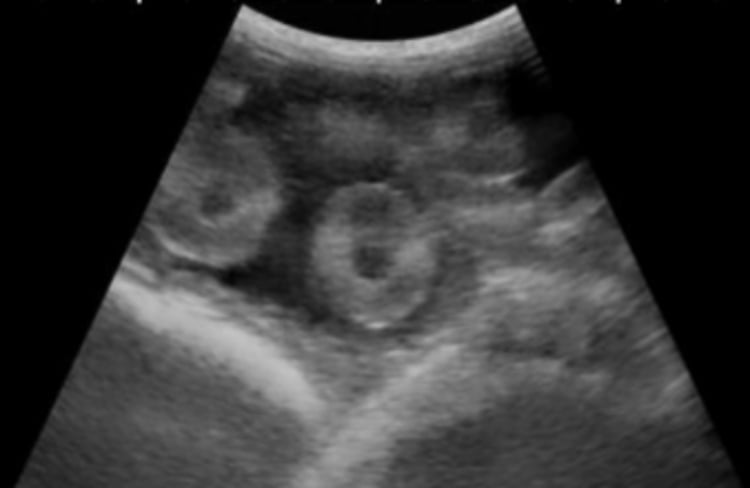

Placentomes, ultrasonogram, ewe

At approximately 55 days of gestation, a transabdominal ultrasonogram of a pregnant ewe typically reveals distinct, developing placentomes, which are the functional units of the small ruminant placenta. At this stage, placentomes are becoming more prominent and are often one of the most recognizable structures on the scan. Placentomes appear as paired, echogenic to moderately echogenic, C‑shaped or O-shaped structures within the uterine lumen.

Courtesy of Dr. Clare Scully.